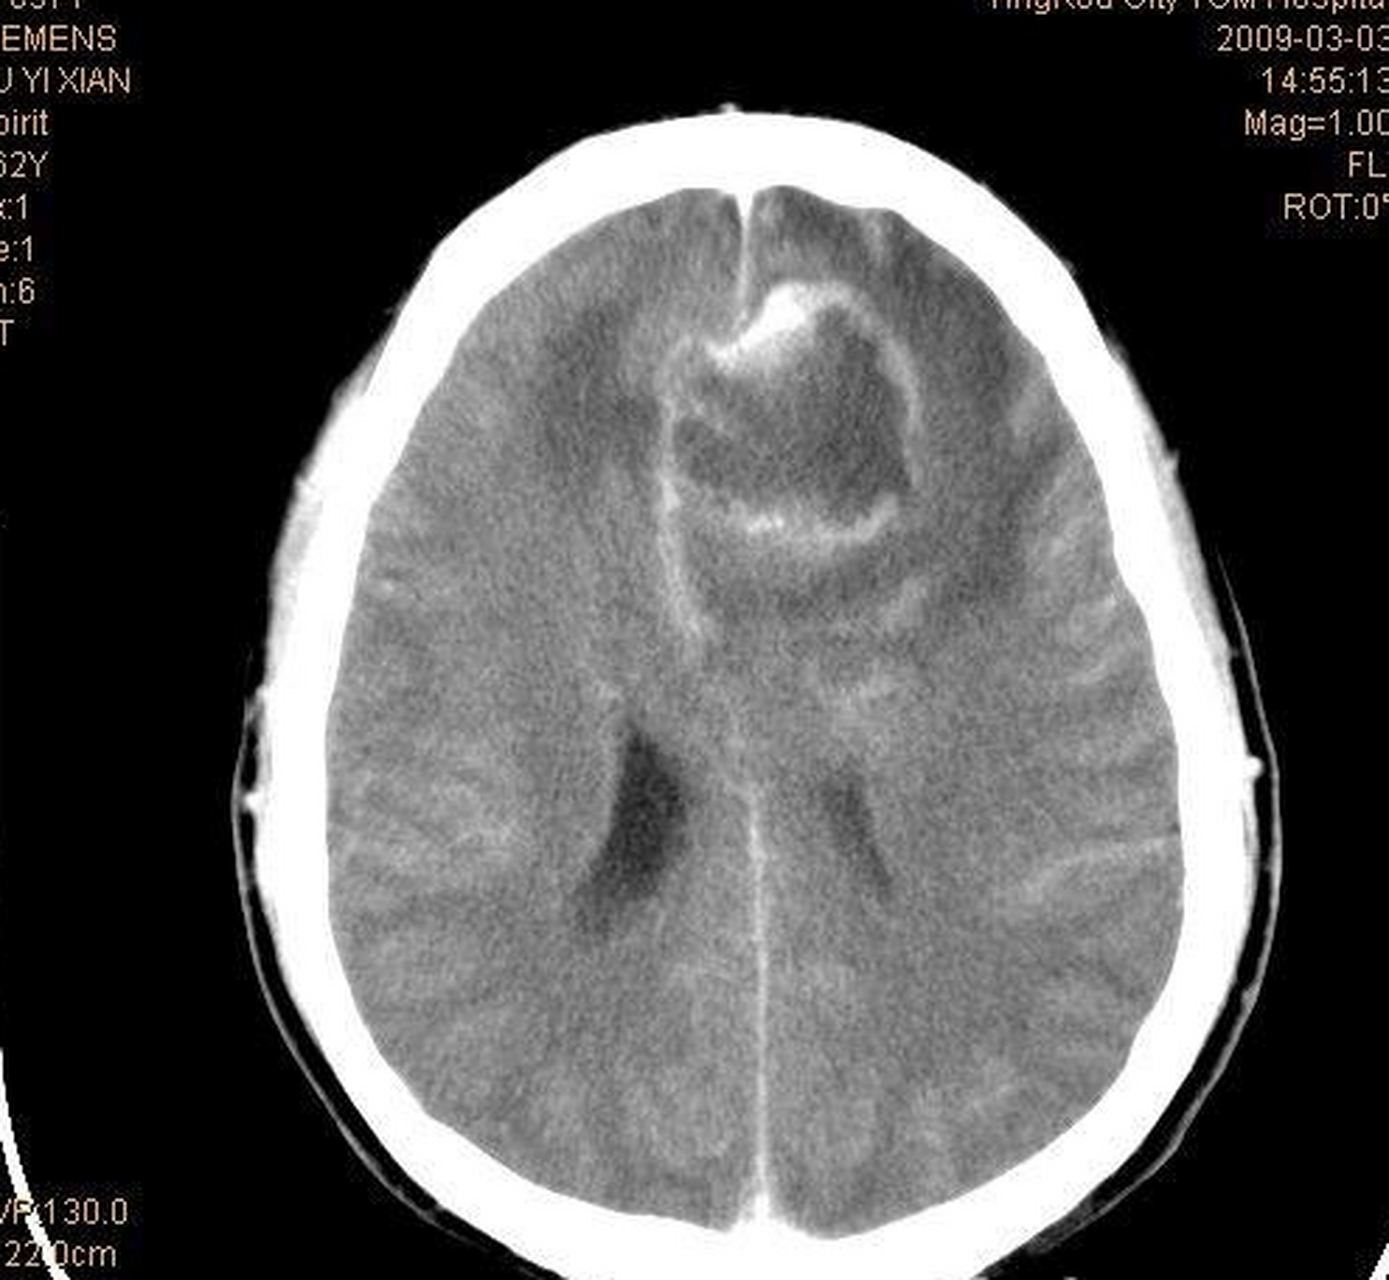

脑肿瘤晚期症状主要包括以下几方面1颅内压增高相关症状脑肿瘤晚期因肿瘤迅速增大及显著脑水肿,颅内压急剧升高最突出的表现为剧烈头痛,常呈持续性加重,尤其在清晨或夜间更为明显,咳嗽弯腰等动作可加剧疼痛呕吐是另一典型症状,多为喷射性,患者常因进食后剧烈呕吐导致无法正常饮食,出现营养不良;脑瘤晚期的症状主要包括以下几方面颅内压升高脑瘤晚期患者常因肿瘤体积增大或脑脊液循环受阻,导致颅内压持续升高典型表现为剧烈头痛,多呈搏动性或持续性,夜间或晨起时加重喷射性呕吐,与进食无关,常因颅内压刺激呕吐中枢引发视乳头水肿,通过眼底检查可发现视盘充血边缘模糊,是颅内压增高的客观;4并发症相关症状晚期患者因长期卧床,局部皮肤受压易引发褥疮好发于骶尾部足跟等部位,表现为皮肤破溃感染免疫力低下易并发肺部感染咳嗽咳痰发热泌尿系统感染尿频尿急尿痛等部分患者可能因深静脉血栓形成导致肺栓塞突发胸痛呼吸困难需注意,脑肿瘤晚期症状因肿瘤;脑肿瘤晚期会出现多种症状,具体如下一神经系统症状 颅内压增高表现肿瘤体积增大使颅内压急剧升高,患者常出现剧烈头痛,多为持续性胀痛或跳痛,清晨加重,伴恶心喷射性呕吐因视神经受压,视力减退甚至失明,眼底检查可见视神经乳头水肿儿童因颅缝未闭合,可能出现头颅增大囟门隆起癫痫发作。

1颅内压急剧升高相关症状脑瘤晚期因肿瘤体积巨大及广泛性脑组织水肿,颅内压会显著升高患者常表现为持续性剧烈头痛,疼痛程度较之前明显加重,可能伴随头昏恶心,且频繁呕吐呕吐物多为胃内容物由于颅内压持续增高,可能引发视乳头水肿,导致视力急剧下降,甚至出现视野缺损如只能看到前方物体,两;脑瘤晚期患者的主要症状表现如下1严重的肢体与言语功能障碍晚期脑肿瘤会直接压迫或侵犯大脑运动区语言中枢等关键功能区,导致患者出现偏瘫肢体无力,甚至完全丧失运动能力语言功能受损表现为失语无法表达或理解语言构音障碍发音模糊等这些症状通常呈进行性加重,严重影响患者日常生活能力2;颅内压增高相关症状脑瘤晚期常因肿瘤体积增大或脑组织水肿导致颅内压持续升高典型表现为剧烈头痛常呈搏动性,晨起或夜间加重喷射性呕吐与进食无关视乳头水肿眼底检查可见视盘边界模糊若颅内压急剧升高,可能引发脑疝,导致呼吸骤停或昏迷神经功能损伤表现肿瘤位置直接影响神经功能受损类型。

其他感官及系统症状肿瘤压迫听神经可导致听力下降或耳鸣侵犯嗅神经引发嗅觉丧失或幻嗅若影响下丘脑或垂体,可出现内分泌紊乱如尿崩症性功能减退晚期患者还可能因长期卧床出现消瘦乏力等全身消耗症状脑瘤晚期症状进展迅速且个体差异大,需通过影像学检查如MRICT及病理活检明确诊断 及时;日常护理要点需保持呼吸道通畅,及时清除口腔和鼻腔分泌物,防止误吸避免剧烈运动和情绪激动,减少颅内压波动遵医嘱使用脱水剂如甘露醇呋塞米降低颅内压密切观察病情变化,若出现头痛加剧呕吐频繁视力下降等症状,需立即告知医生调整治疗方案脑肿瘤晚期症状多与颅内压增高相关,及时干预可。